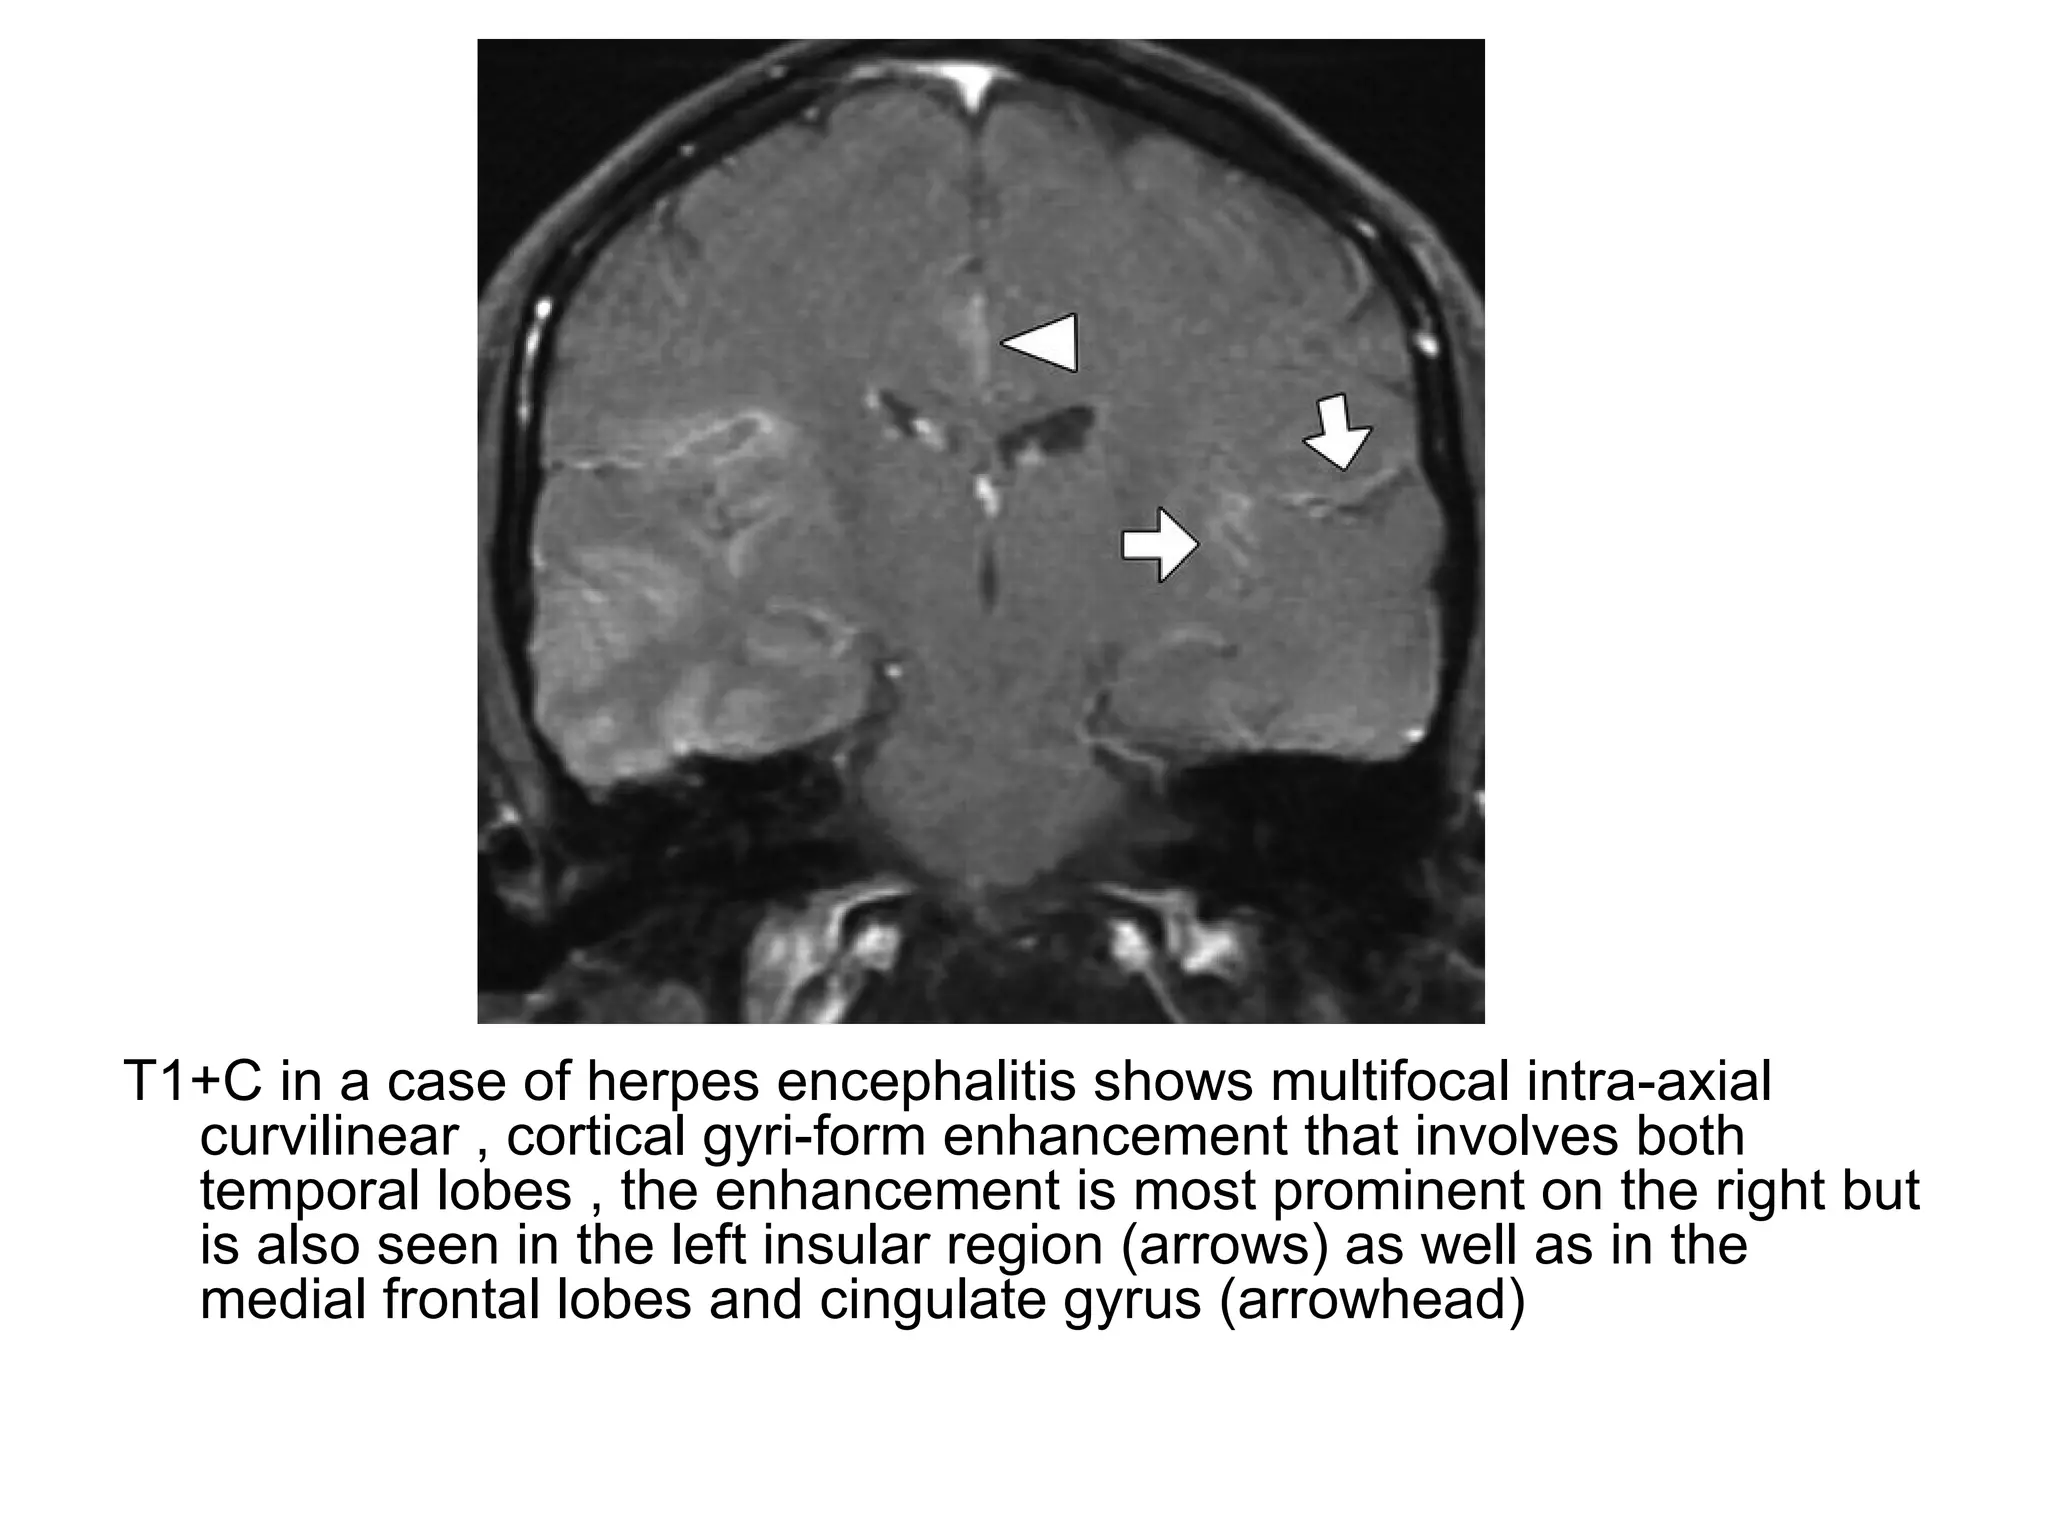

T1+C in a case of herpes encephalitis shows multifocal intra-axial

curvilinear , cortical gyri-form enhancement that involves both

temporal lobes , the enhancement is most prominent on the right but

is also seen in the left insular region (arrows) as well as in the

medial frontal lobes and cingulate gyrus (arrowhead)